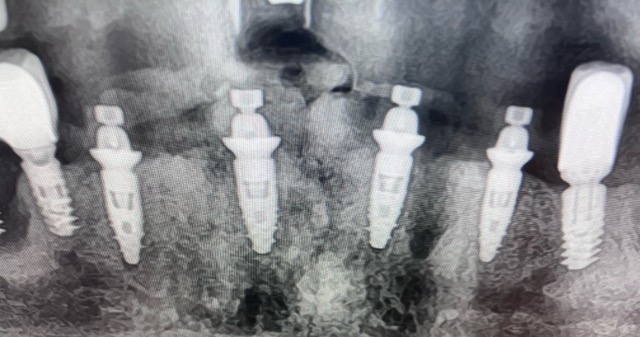

Peut-on remplacer ses dents en une seule journée ? Oui. Grâce à l’implantologie immédiate, il est possible de réaliser les extractions, poser les implants et fixer un bridge provisoire dans la même journée.

Exemple réel : chirurgie terminée à 11h — sourire fixé à 16h.

2. Pose immédiate des implants avec stabilité primaire élevée.

Ce protocole nécessite une sélection précise : volume osseux suffisant, stabilité des implants et

planification numérique (scanner 3D + empreinte).